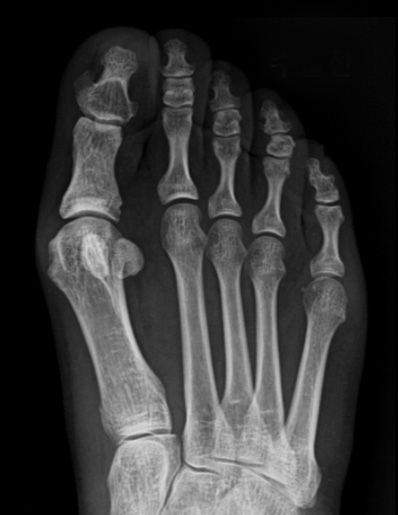

근위 중족골 절골술과 스카프 절골술의 경우 교정력이 좋기 때문에 주로 중증 무지외반증에 적용합니다.

개방형 원위 절골술의 경우 절골 방법은 MICA 와 비슷하지만 조금 더 안정적이고 절개가 크지 않으면서

연부조직의 처리가 같이 가능하기 때문에 필요한 경우 적용할 수 있습니다.

절개 수술법의 경우 큰 각도의 변형을 교정할 수 있습니다.

첫번째 사진을 보면 중족골두에서 근위지골의 기저부가 완전히 벗어나 있는 것을 확인할 수 있고,

수술 후에는 관절이 잘 맞아 들어간 것을 확인할 수 있습니다.